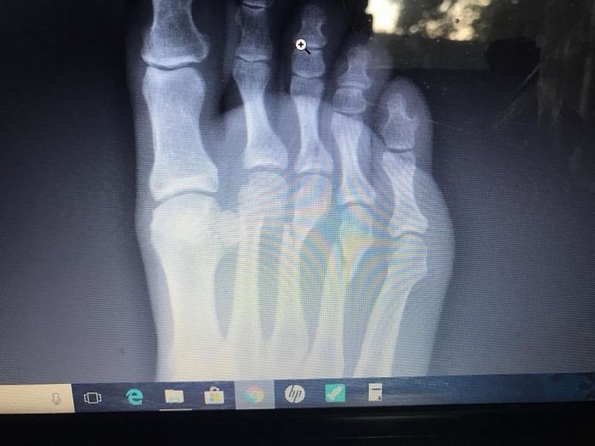

Дејвид ја притиснал инстиктивно кочницата толку јако, што ги скршил трите предни коски на неговото десно стапало. За среќа, нема да му е потребна операција, но не смее да чекори на неговото десно стапало во времетраење од 6-8 седмици.